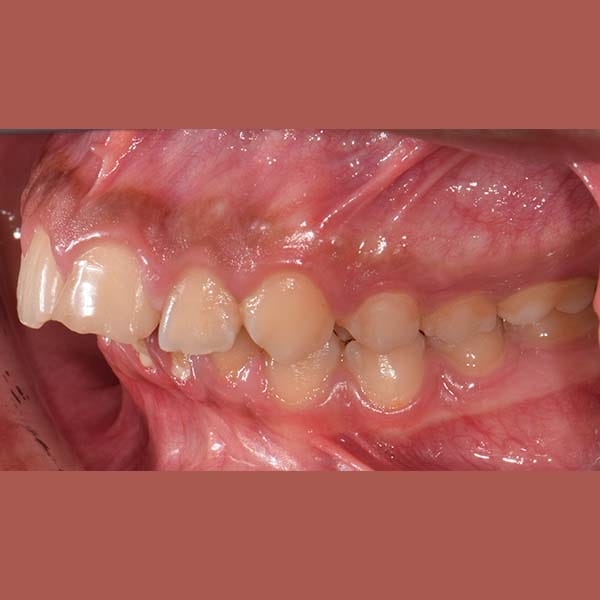

عندما يكون بروز الأسنان ناتجاً عن تراجع الفك السفلي، يمكن للتدخل المبكر أن يحل المشكلة من جذورها. بصفتي أخصائي تقويم أسنان في العين، أستخدم الأجهزة الوظيفية لتصحيح علاقة الفكين. هذه الحالة توضح كيفية علاج بروز الأسنان بدون خلع باستخدام جهاز وظيفي ثابت.

عانى هذا الشاب اليافع من بروز في الأسنان الأمامية العلوية بسبب تراجع الفك السفلي. أثرت هذه المشكلة على قدرته على قطع الطعام بشكل جيد، بالإضافة إلى شعوره بالخجل من الابتسام أمام أصدقائه في المدرسة.

كما تظهر الصور، تم تصحيح البروز وتراجع الفك السفلي بنجاح. أصبح بإمكان صديقنا الآن أن يبتسم بثقة، والأهم من ذلك، أن يأكل ما لذ وطاب من دون أي مشاكل في القضم.